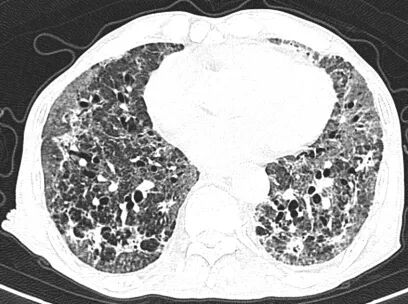

患者王大爷因“咳嗽、胸闷3天,呼吸困难加重5小时”被120紧急送入本部院区就诊。入院时患者高热、呼吸极度困难,肺部听诊可闻广泛Velcro啰音,血气分析提示Ⅰ型呼吸衰竭,胸部CT显示双肺弥漫性结节斑片影。患者有溃疡性结肠炎病史,曾使用激素治疗,初步诊断为重症肺炎。病情危急,医疗团队立即予以高流量氧疗、抗感染及激素治疗,并由贾兆广副主任医师行床旁气管镜检查,送检支气管灌洗液进行tNGS病原学检测。

胸部CT:双肺弥漫结节斑片影